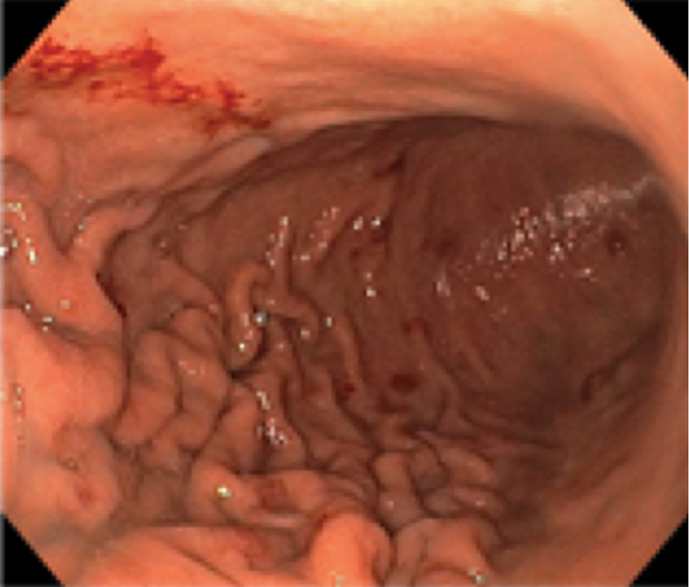

Case description: A 56-year-old male presented with 2 months of abdominal pain, distension, fatigue, and weight loss. Imaging revealed multifocal hypodense liver and splenic lesions. Laboratory findings included severe anemia (Hb 6.1 g/dL), thrombocytopenia (63 × 103/mm3), and elevated liver enzymes. Ascitic fluid analysis demonstrated exudative, bloody ascites (SAAG <1.1) without malignant cytology. Liver biopsy confirmed HAS, showing atypical spindle cells infiltrating vascular channels, positive for CD34 and factor VIII. Despite transfusions, paracentesis, and palliative care, the patient developed disseminated intravascular coagulation and died 2 weeks post-diagnosis.